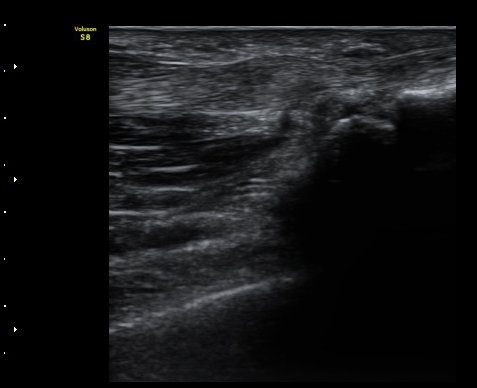

ºÎÁ¾ÀÌ °üÂûµÊ(±×¸² 1, 2). ÈûÁ٠Ⱦ´Ü¸é°Ë»ç¿¡¼­ A1ȰÂ÷ÀÇ Àú¿¡ÄÚ ºÎÁ¾ÀÌ °üÃÔµÊ(±×¸² 3).

¼Õ°¡¶ô ½ÅÀü ½Ã ºÎÀº ÈûÁÙÀÌ a1ÇÒÂ÷¸¦ Åë°úÇÏÁö ¸øÇÏ°í °É¸°´Â ¸ð½ÀÀÌ °üÂûµÊ(±×¸² 4).

ÈûÁÙÀÌ °É¸®´Â ¸ð½ÀÀº µ¿¿µ»ó(÷ºÎ ÆÄÀÏ)¿¡¼­ ¶Ñ·ÈÈ÷ °üÂûµÊ.